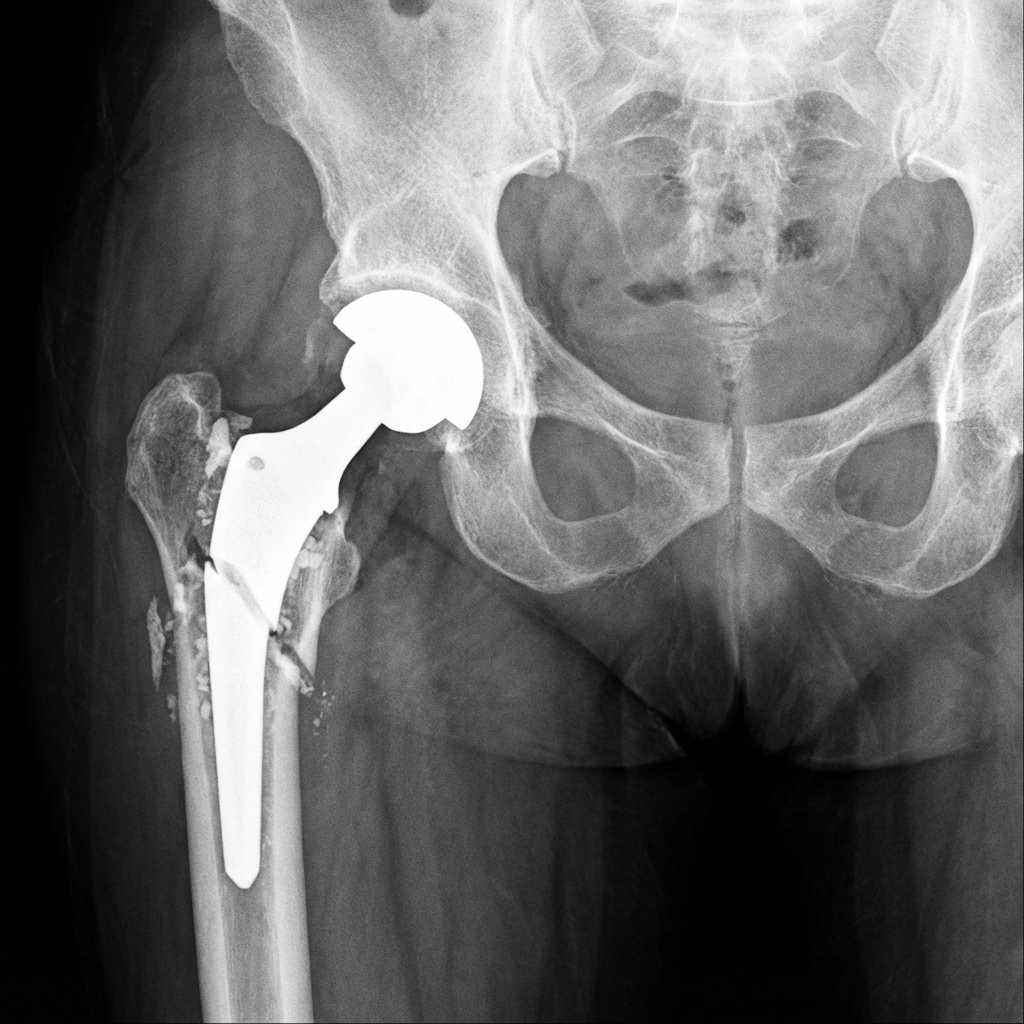

AP pelvis radiograph demonstrating periprosthetic femur fracture around a cemented total hip arthroplasty. The fracture is at the level of the stem tip with oblique pattern extending proximally. Evidence of cement mantle fracture and possible stem subsidence. The patient had pre-injury pain suggesting loosening. This is a Vancouver B2 pattern requiring revision arthroplasty.